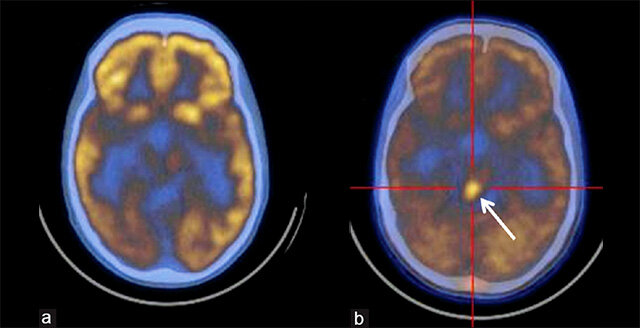

Для ПЭТ КТ его помечают углеродом 11. Этот радиофармпрепарат позволяет выявлять метаболические характеристики структурного поражения головного мозга. Главным показателем опухолевого процесса становится высокое накопление 11С -метионина в области, где располагается первичная опухоль. Диагностический метод позволяет отследить изменения в динамике, в том числе после проведения лечения. В месте где проходило лучевое иссечение опухоли, повышенное содержание препарата не отмечается, на участках некроза оно даже снижено.